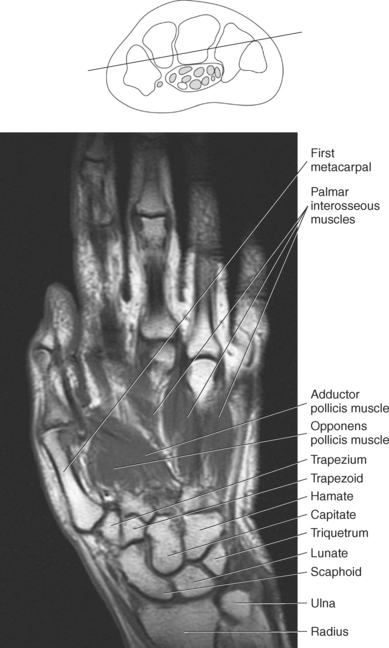

The muscles of the hand can be divided into three groups: (1) metacarpal group (muscles of the metacarpals considered to be the central muscles of the hand), (2) thenar group (muscles involving the thumb and creating the thenar eminence on the radial side), (3) hypothenar group (muscles involving the fifth digit and creating the hypothenar eminence on the ulnar side). These muscles are demonstrated in Figures 9.128 through 9.143.

The metacarpal muscle group includes the interossei and lumbrical muscles. There are seven short interossei muscles in the metacarpal muscle group: three single-headed muscles located on the palmar surface and four double-headed muscles located on the dorsal surface (Figure 9.141, A and B). The four palmar interossei muscles arise from the first, second, fourth, and fifth metacarpals and insert on the corresponding proximal phalanges, frequently radiating into the corresponding tendons of the dorsal aponeurosis. These muscles are responsible for flexion at the MCP joints and extension at the interphalangeal joints. The dorsal interossei arise by two heads from the sides of the five metacarpal bones to insert on the proximal phalanges and radiate onto the dorsal aponeurosis. Like their palmar counterparts, the dorsal interossei flex at the MCP joints and extend at the interphalangeal joints. The four small lumbrical muscles arise from the tendons of the flexor digitorum profundus and pass to the radial side of the corresponding finger to insert on the extensor expansion covering the dorsal surface of the finger (Figure 9.142). The lumbricals flex the first phalanges at the MCP joints and extend the second and third phalanges at the interphalangeal joints.

The four muscles of the thenar group are the abductor pollicis brevis, flexor pollicis brevis, adductor pollicis, and opponens pollicis. The abductor pollicis brevis is a thin, flat superficial muscle arising from the transverse carpal ligament, navicular, and trapezium (Figure 9.143). It runs inferiorly and laterally to insert on the base of the first phalanx of the thumb to abduct the thumb. The flexor pollicis brevis has two heads: The superficial or lateral head arises from the flexor retinaculum, and the deep or medial head arises from the trapezium, trapezoid, and capitate. This muscle inserts on the radial and ulnar base of the first phalanx to flex, adduct, and abduct the thumb (Figure 9.143). Frequently, a sesamoid bone can be found in the insertion tendon on the radial side. The adductor pollicis also has two heads: The transverse head arises from the dorsal aspect of the third metacarpal, and the oblique head arises from numerous slips off the capitate, bases of the second and third metacarpals, and the sheath of the flexor carpi radialis tendon. The adductor pollicis inserts onto the base of the first phalanx of the thumb to provide adduction and assist in the opposition and flexion of the thumb (Figures 9.142 and 9.143). The opponens pollicis provides the main opposition for the thumb but also assists with adduction. It arises from the trapezium and flexor retinaculum and inserts onto the radial aspect of the first metacarpal (Figures 9.142 and 9.143). These muscles are also demonstrated in sequential Figures 9.128 through 9.140.

The hypothenar group consists of three muscles: abductor digiti minimi, flexor digiti minimi brevis, and opponens digiti minimi. The abductor digiti minimi muscle arises from the pisiform and the flexor retinaculum to end in a flat tendon that inserts onto the ulnar base of the first phalanx of the little finger (Figures 9.142 and 9.143). The abductor digiti minimi muscle is the main abductor of the little finger. The flexor digiti minimi brevis muscle arises from the flexor retinaculum and the hook of the hamate. It fuses with the tendon of the abductor digiti minimi to insert on the base of the first phalanx of the fifth digit (Figures 9.142 and 9.143). The flexor digiti minimi brevis flexes at the MCP joint. Like the flexor digiti minimi brevis muscle, the opponens digiti minimi arises from the hook of the hamate and the flexor retinaculum (Figure 9.143). It inserts on the ulnar surface of the fifth metacarpal to bring the little finger into the position for opposition. For the hand muscles, see Figures 9.128 through 9.140.